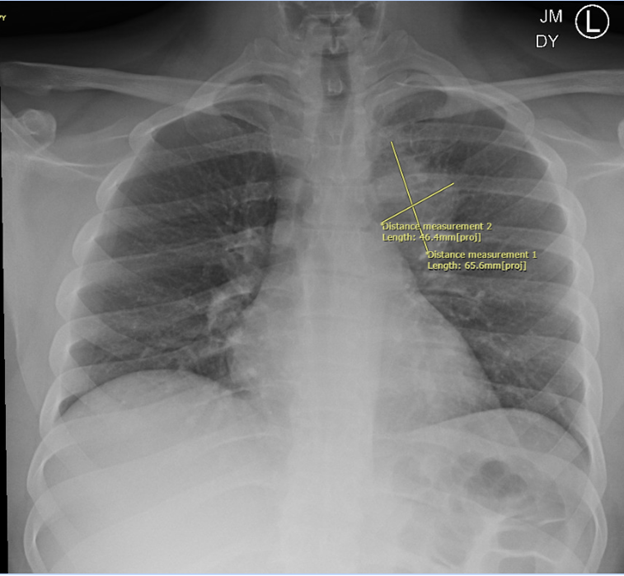

Case Presentation: Case: A 27-year-old male presented to the emergency room with fever, night sweats, and productive cough with brown sputum for the past week prior to presentation. He also noted associated anorexia, nausea, and non-bilious, non-bloody vomiting. The patient reported persistent dysphagia that had developed after his laryngeal schwannoma resection 15 years ago. On presentation, he was febrile to 100.4 degrees Fahrenheit, tachycardic to 102 beats per minute, and tachypneic to 37 breaths per minute. Physical exam was within normal limits. Labs were notable for neutrophil-predominant leukocytosis (WBC: 14.37 × 109/L) and elevated inflammatory markers. Computerized tomography of the chest demonstrated a focal necrotic air-filled lesion in the posterior left upper lobe consistent with lung abscess. The patient was admitted for management of lung abscess with parenteral antibiotics. He was started on ampicillin-sulbactam and demonstrated substantial clinical improvement. Sputum cultures grew normal respiratory flora. Videofluoroscopic swallowing study demonstrated moderately compensated oropharyngeal dysphagia. His course was complicated by drug-induced liver injury secondary to ampicillin-sulbactam and was switched to a four-week course of levofloxacin and metronidazole. He was discharged with close follow-up with his primary care provider, otolaryngology, pulmonology, and speech and language pathology.